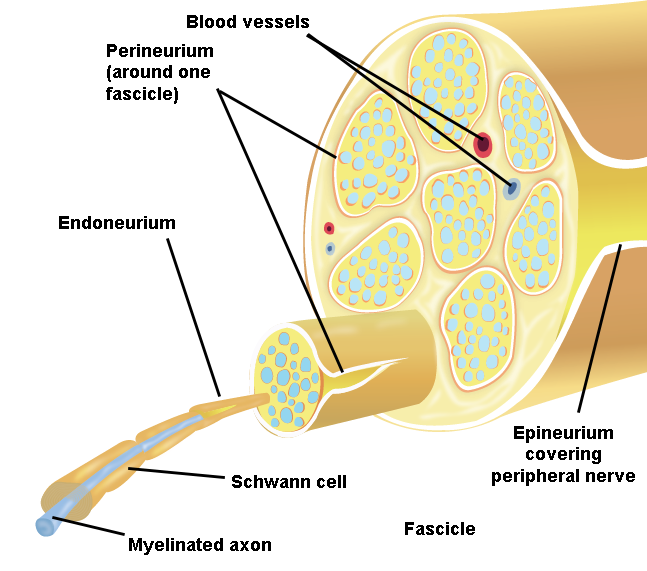

Illustration 1. Anatomy of Peripheral Nerves

II. Anatomy of Peripheral Nerves

Peripheral nerves are composed of bundles of neurons, or nerve fascicles, which are enclosed by a connective tissue called the perineurium.

- Fascicles are further bundled and held together by the loose connective tissue of the endoneurium.

- This nerve complex is enclosed within epineurium, the outermost layer of a peripheral nerve.